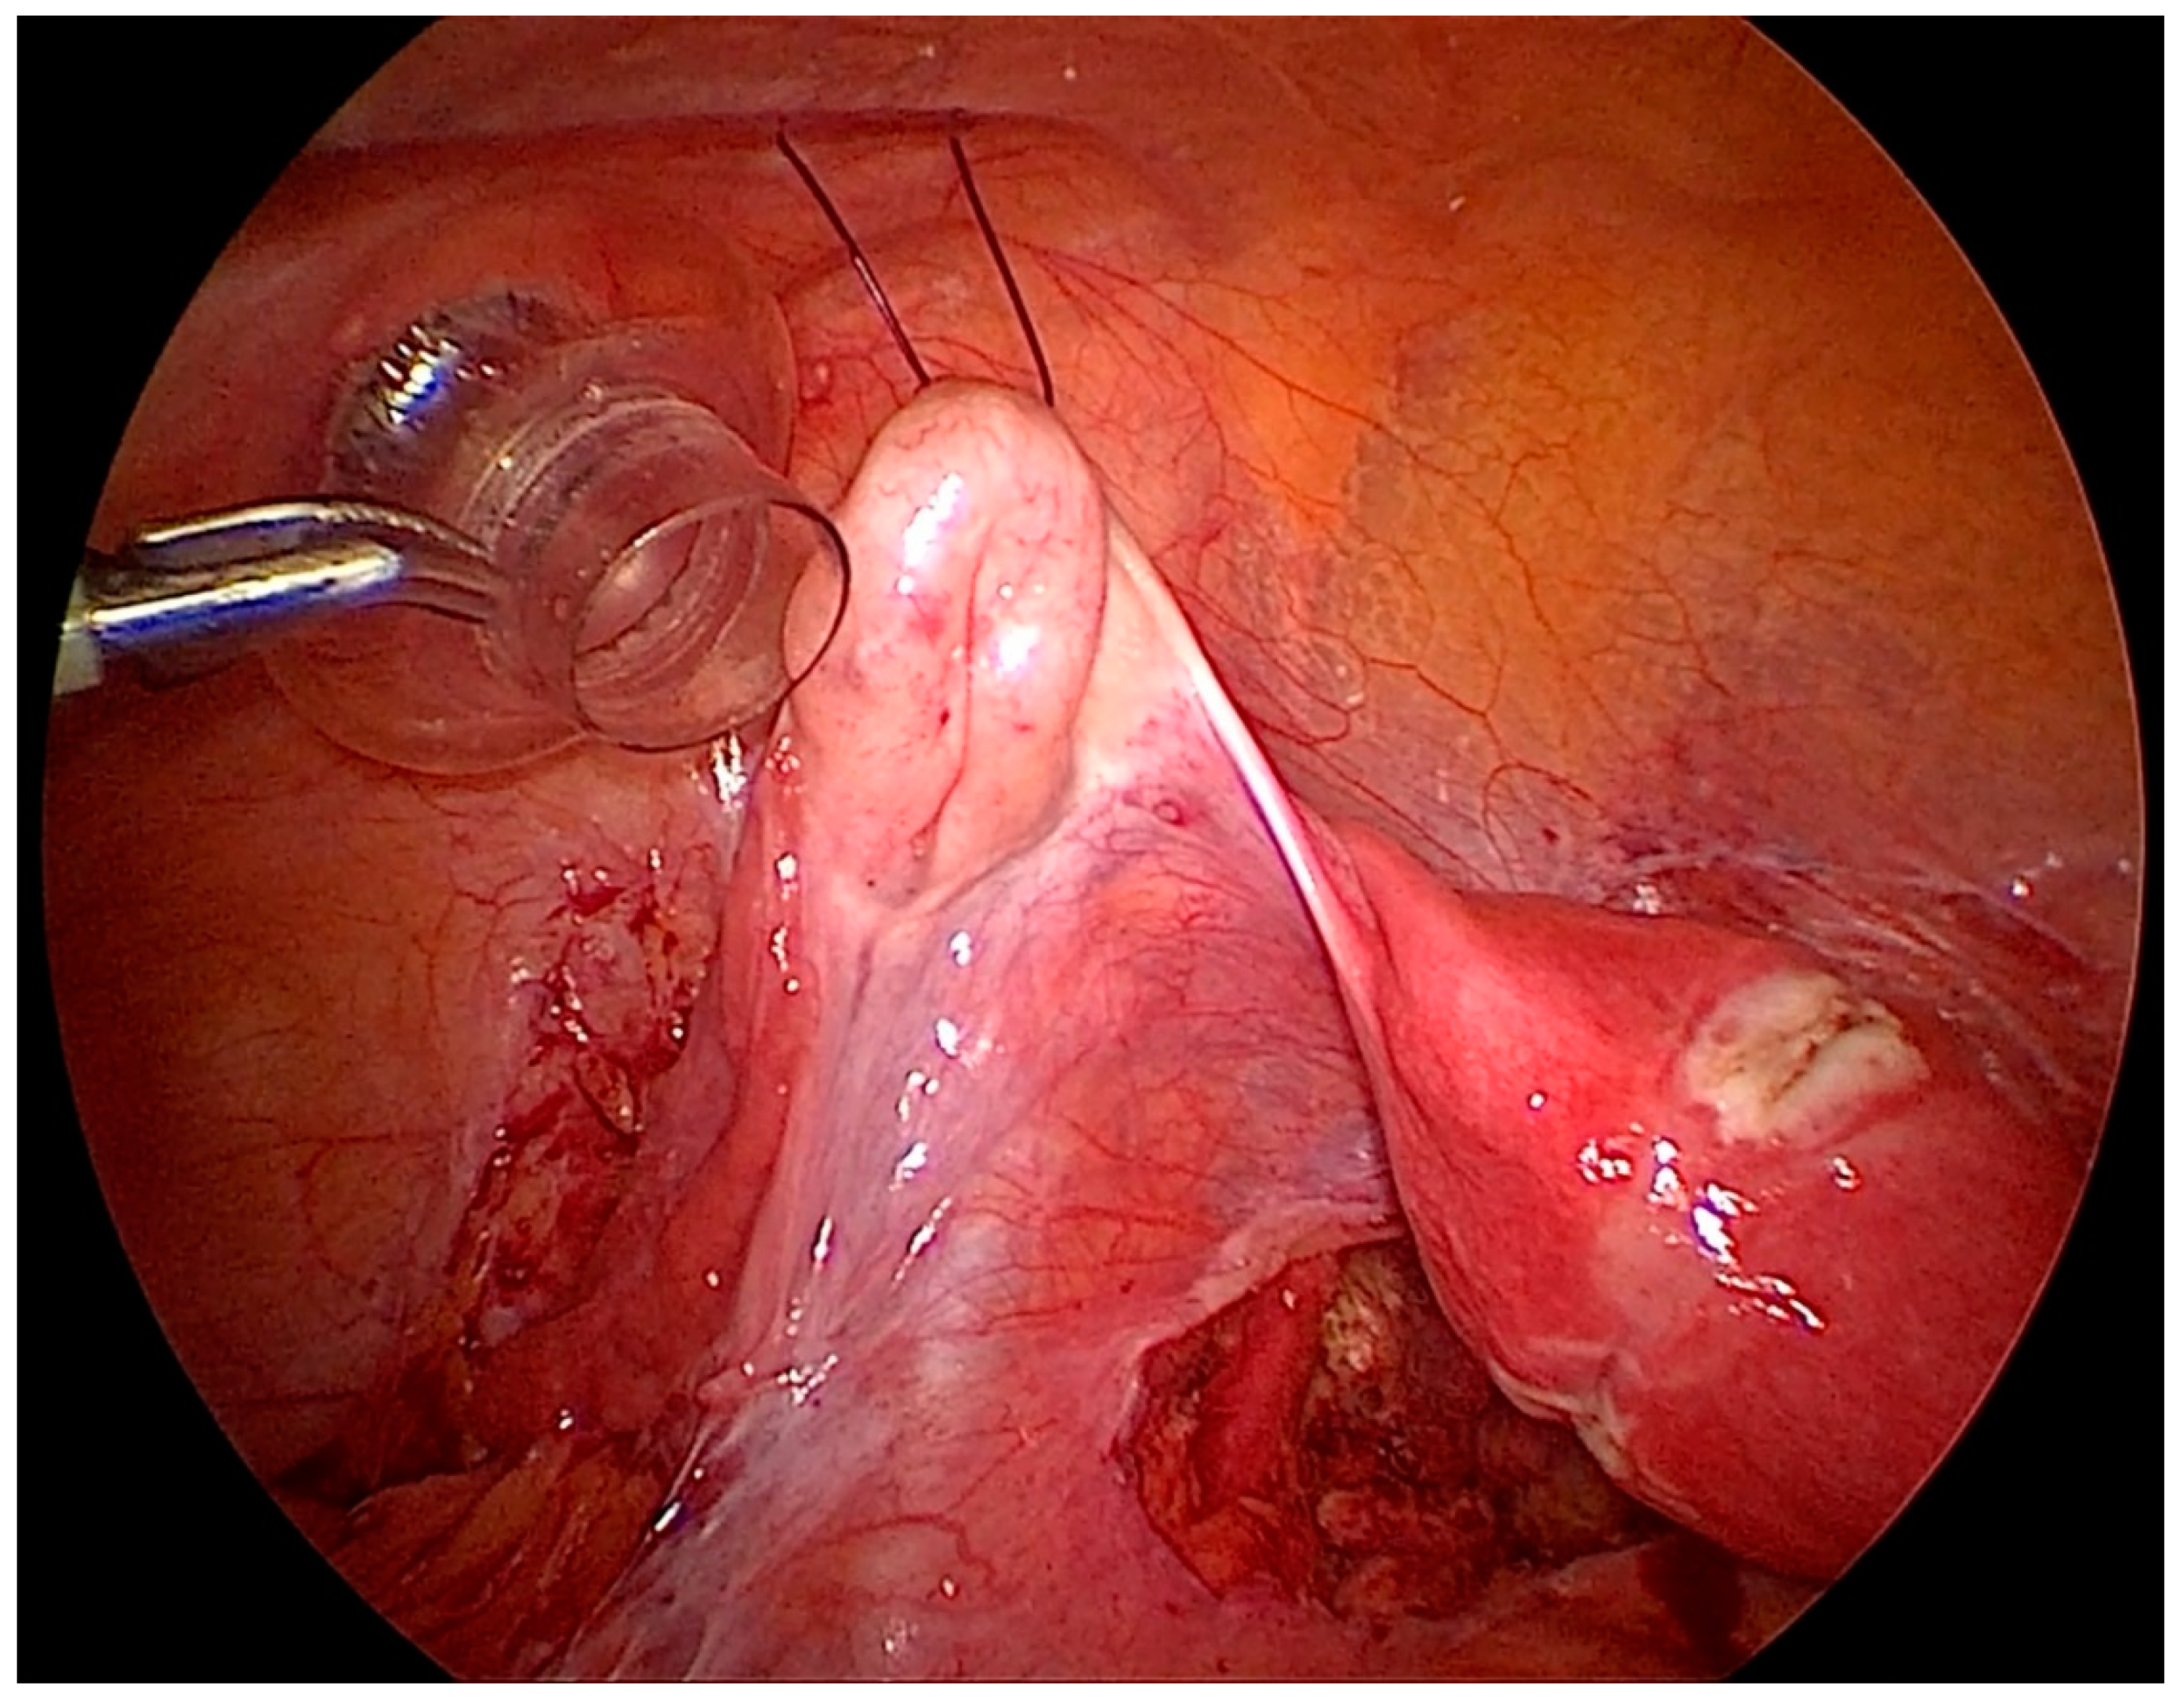

Another illustration after endometriosis resection with the important anatomical structures shown (Figure 4). Vessels in the abdominal wall have to be kept in mind before doing an ovariopexy to prevent puncture of it [29]. Comfortable access to the lateral pelvic wall is really important to prevent damage to major structures like the ureter and uterine artery, a very common site for superficial and deep endometriosis.

Figure 4.

Illustration showing left suspended ovary to the anterior abdominal wall after endometriosis surgery with important anatomical structures. (A) Inferior epigastric vessels in the lateral umbilical fold. (B) Medial umbilical ligament. (C) Uterine Artery. (D) Ureter.